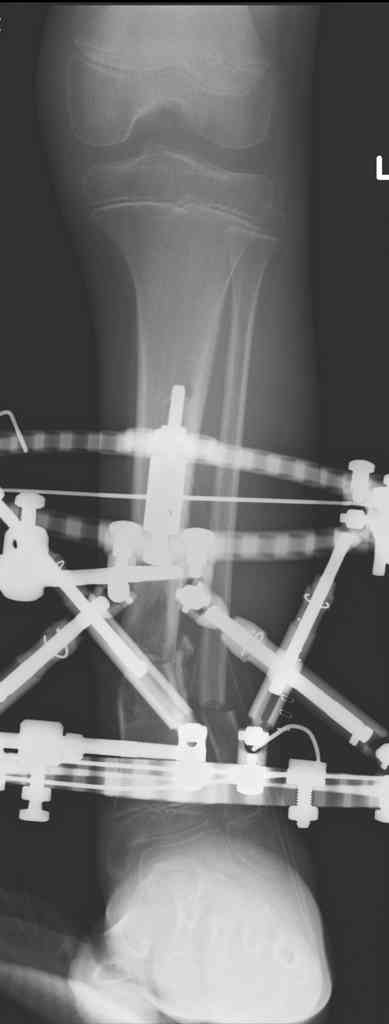

Another choice is simply perform shortening + posterior angulation with Ilizarov or TSF , than gradual correction of the angulation.After all apply third ring on the proximal tibia and start lengthening.

We had recently similar case in 14 years old boy with 45 mm bone defect after open tibial fracture.Boy doing excellent .This technique is not new, Sasha Lerner did it in Rambam , Rozbruch wrote also.

Another advantage of this techniqe is relaxation of soft tissue and possibility for closure even large defects of the skin.In your case I will apply ring on the foot and mid diaphysis of the tibia ,removal of the fibular plate,sindesmotic wire, and after correction of angulation on the proximal tibia.